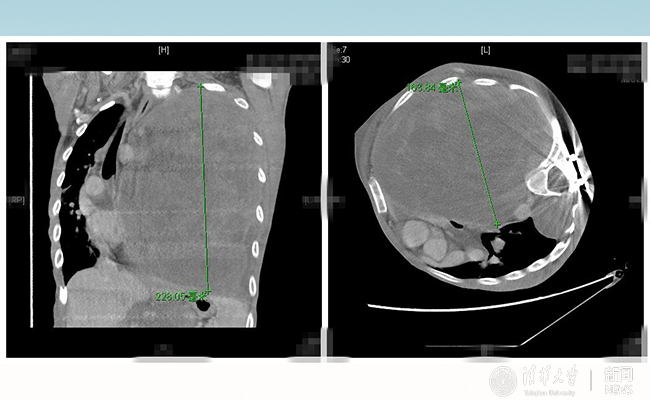

清华长庚医院多学科助力胸外科手术,成功帮28岁的患者“小飞”切除巨型神经纤维瘤,帮助重病的患者重生。